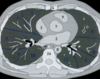

Imagen de TC de alta resolución que muestra fibrosis pulmonar.

Principales utilidades de TC de alta resolución son:

• Valorar el grado de afectación de enfermedades intersticiales pulmonares.

• En pacientes EPOC, para valorar el grado de enfisema y pequeñas zonas de atrapamiento aéreo.

• Determinar la gravedad y extensión de bronquiectasias.

• Valorar qué área es más rentable biopsiar.